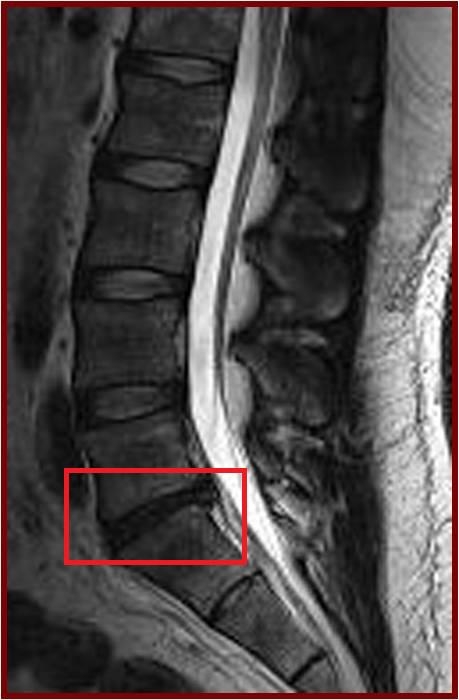

世界各地人口都受腰痛影響,而腰痛亦是為香港勞動人口造成不健康及病假的主要原因。導致腰痛的其中一個主要原因是脊椎的關節,即椎間盤出現退化。香港大學李嘉誠醫學院矯形及創傷外科學系一項研究發現,肥胖的成年人出現椎間盤退化及發展成更嚴重的病徵的機會,較正常體重的成年人高一倍。是次研究內容是值得大眾關注的健康課題,其研究結果已刊登於最新一期的權威醫學期刊《Arthritis and Rheumatism》。

傳統醫學相信,椎間盤退化是因老化而起,但香港大學研究人員發現過重及肥胖對成年人椎間盤退化有莫大影響,這是一個嶄新的發現。椎間盤退化是不可逆轉的,會為患者帶來長遠的影響及痛苦,例如導致嚴重腰痛,令患者未能如常工作和社交。因此,如有過重及肥胖的跡象的人士,應減輕體重以避免椎間盤加速退化。

今次的研究是一項以南中國地區人口而作出的具代表性抽樣研究,從上述大型人口群組中抽出21歲或以上的成年人為研究對象。在是次的研究中,研究人員分析了合共2,599位成年人的磁力共振(MRI)檢查數據。當中27%(709人)沒有椎間盤退化,而73%(1,809人)則有椎間盤退化。在患有椎間盤退化的成年人當中,有7%體重過輕,48%體重正常,36%過重和9%肥胖。超重及肥胖的成年人出現椎間盤退化程度及發展成更嚴重的病徵的機會,比正常體重或過輕的成年人嚴重。